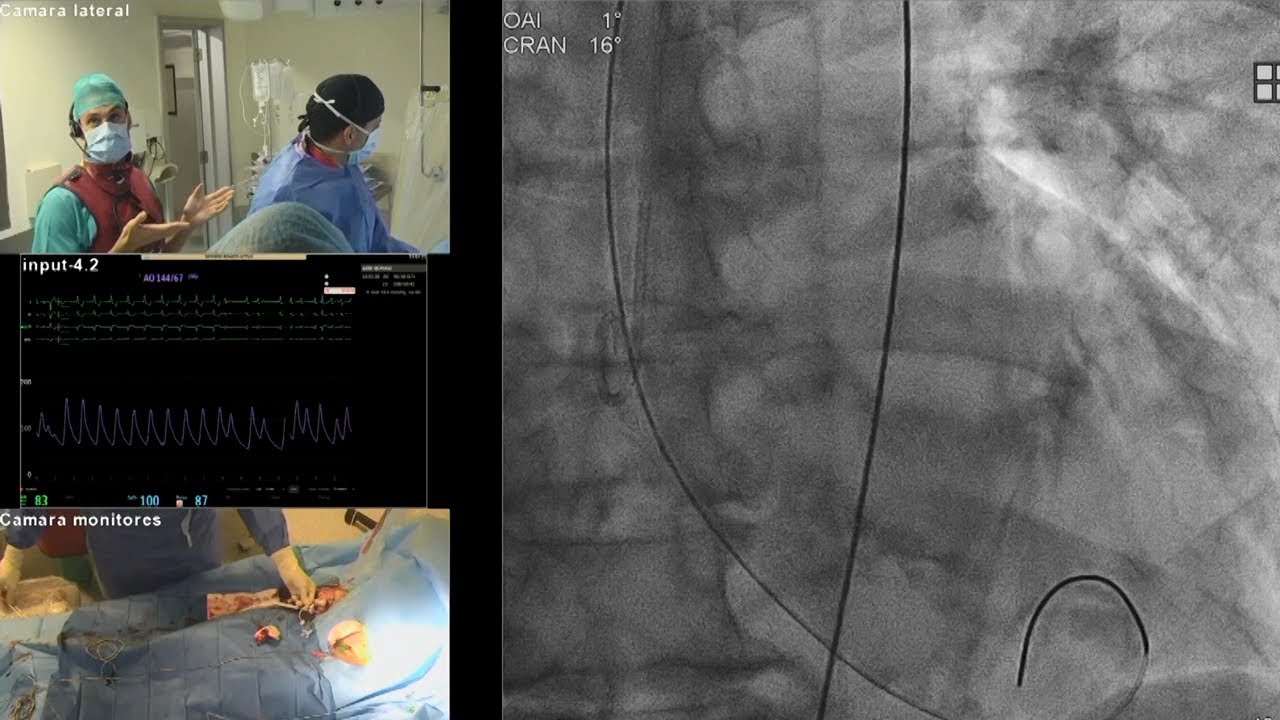

Complex PCI for stent failure: LIVE Educational Case from Hospital Clínico San Carlos - Madrid, Spain

Complex multivessel disease: LIVE Educational Case from Hospital Clínico San Carlos - Madrid, Spain